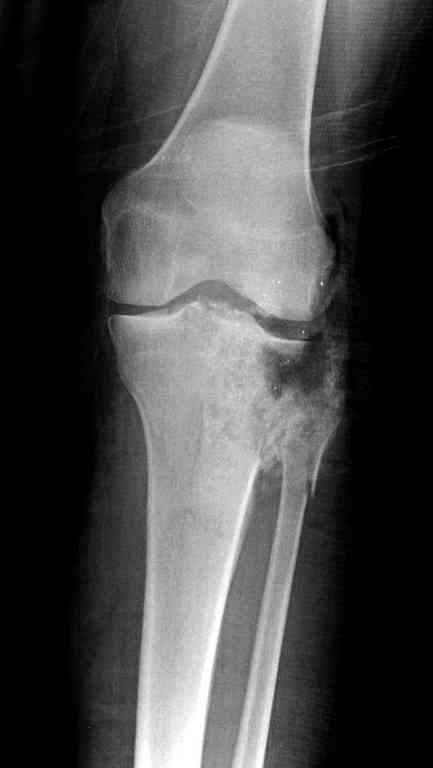

Одинокий кортикальный шуруп не удержит тибиальный бугор, сустав тибиал плато оставлен без репозиции и фиксации.

План с протезированием чересчур агрессивный, больная слишком молодая. В данный момент для удержания конструкции необходимо установить наружный фиксатор между бедром и голенью. Обработку продолжать с применением антибиотиков и вакуумирования.

Здесь применение материала Plexur http://www.plexur.com для пластики при дефектах кости у больной с огнестрельной раной латерального тибиал плато с повреждением малоберцового нерва. Несмотря на интактный медиальный мышелок, для профилактики от вальгуса установлен АВФ и сделана ангиограмма.

После нескольких обработок и вакуумирования, поэтапно сделана фиксация тибиального бугра шурупами. И окончательную фиксацию закончили латеральной пластиной для тибиал плато и установкой пластического материала.